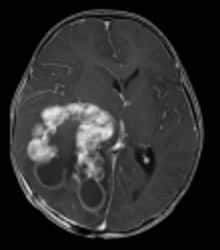

毛様細胞性星細胞腫 | 上衣腫 | 髄芽腫 | 脳幹部腫瘍 |

胚細胞性腫瘍 | 脈絡叢乳頭腫 | 頭蓋咽頭腫 | その他の小児脳腫瘍 |